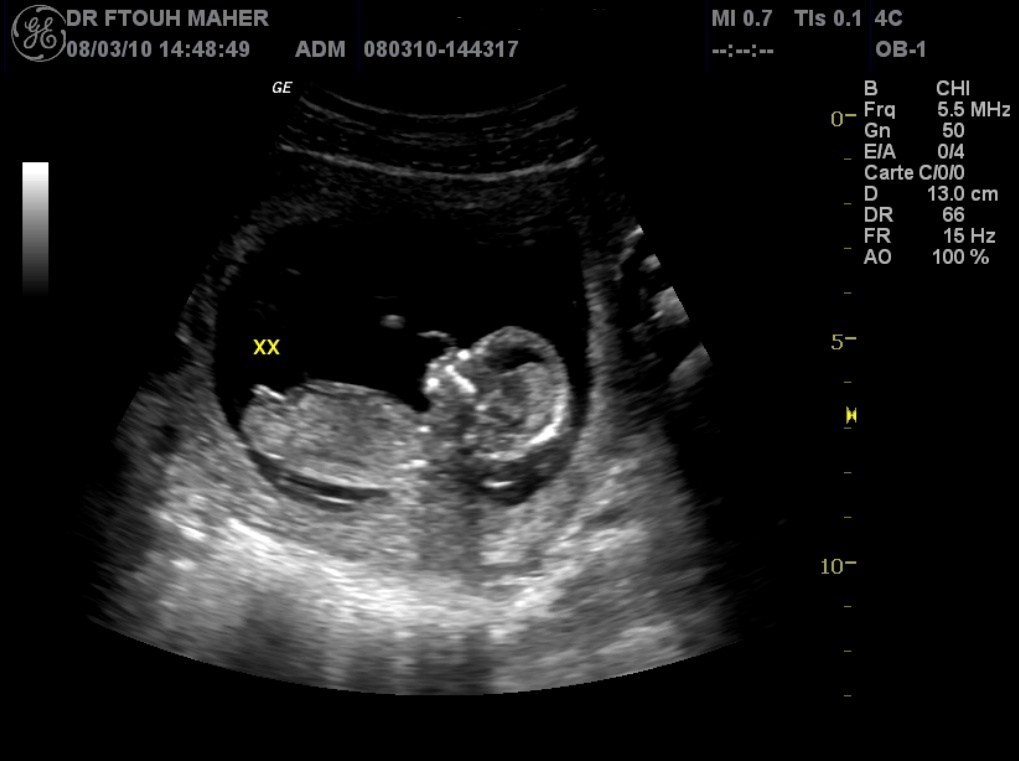

Embryon De 7 Semaines D Amenorrhee Et 2 Jours Activite Cardiaque Et Circulation Vitelline

Echo A 7 Semaines Et 4 Jours D Amenorrhee Bidiblog

Embryon De 7 Semaines Youtube